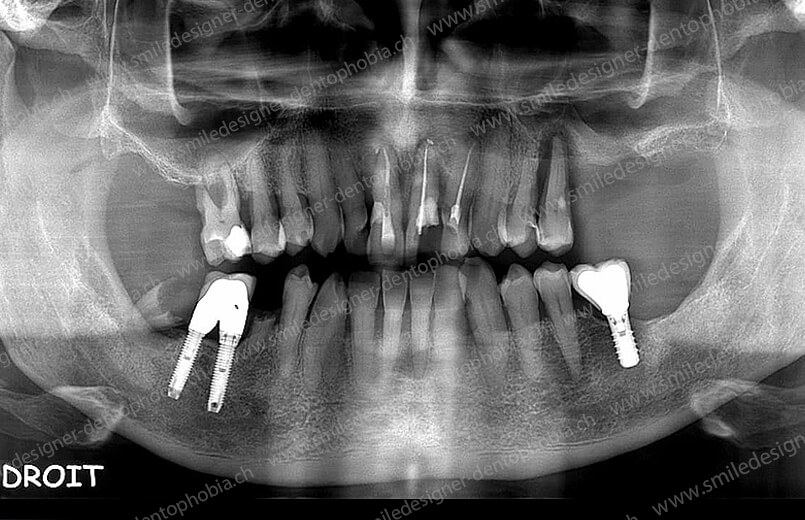

Cas clinique « DOMINO SURGERIES MCI » : Bridge implanto-porté sans extension postérieure (ALL ON 10/8). Version définitive des bridges avec un cosmétique en céramique. Double comblements de sinus et double greffes osseuses d’apposition pour la reconstruction du maxillaire.

Cas clinique « DOMINO SURGERIES MCI » : Bridge implanto-porté sans extension postérieure (ALL ON 8/6). Version définitive des bridges avec un cosmétique en céramique. Double comblements de sinus et double greffes osseuses d’apposition pour la reconstruction du maxillaire.

Cas clinique « DOMINO SURGERIES MCI » : Bridge implanto-porté avec extensions postérieures (ALL ON 6/6).